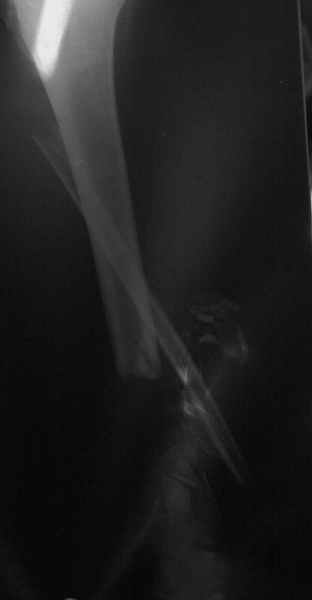

Dorogie kollegy,Have a nice day,Ja bi hotil obsuzdat' s Vami dvuh bolnih, kotorie postupili segodnjia ko mene. Pervy iz nih (OI) bolnoi s otkritoi tiazeloi mehanicheskoi travmoi Rt. leg segment v rezultate DTP, ot chego on imeet sledueshie povrezdenjia:- Otkrity perelom kostei pravoi goleny v srednei i niznoi ee trety s poteriem okolo 10 cm. kostnogo veshestva ot bolshebersovoi kosty, - Povrezdenjia a.tibialis post. s massivnim povrezdeniem zadneoi gruppy musculs goleny,- Malobersovjia kost' imeet segmentarny perelom, ee nizny fragment (kak Vi videte na foto) vistupaet na kozy okolo VNUTRENNOI Lodizky! - Traumaticheski Shock 2-3Drugih povrezdenjia net.

Nemedlenno bolnoi bil' intubirovan i provedeny vse protivoshokovie procedury, pravjia golen' bila pomeshenjia na apparat' Storm, dla reduksii kostei posle ee fiksasii k apparatu s pomoshio 2 spitsy 3mm D. Provedena Repozitsia pereloma i fiksirovana STORMOM vremenno, za tem sosudisty hirurg vypolnil 2 obhodnih anastomosa for a. Tibilis posterior, bili udaleny bolshie chasty iz musculov zadnoi gruppy goleny v predelah "vozmozno vedemih" zdorovoi tkany, oblast' pereloma promita by N. sol. 0.9% - 12 L. Zatem byla proizvedena okonchatenjia reduksia pereloma posle umerennoi traksii goleny na apparate, i fiksasiya pereloma s pomoshio apparata vneshnei fiksasii. Tak, Kakie soobrazanjia po dalneshemu vvdenjia bolnogo? On poluchaet antibiotiky i bolshie dozy LMH (Clexane 80 X 2) i vse ostalnoe......

К сожалению на первичной и последующей рентгенограммах не видно, что творится с голеностопным суставом. Если вилка суства сохранена, то есть смысл побороться за конечность. Интересно, увитеть, что твориться с голеностопным суставом.